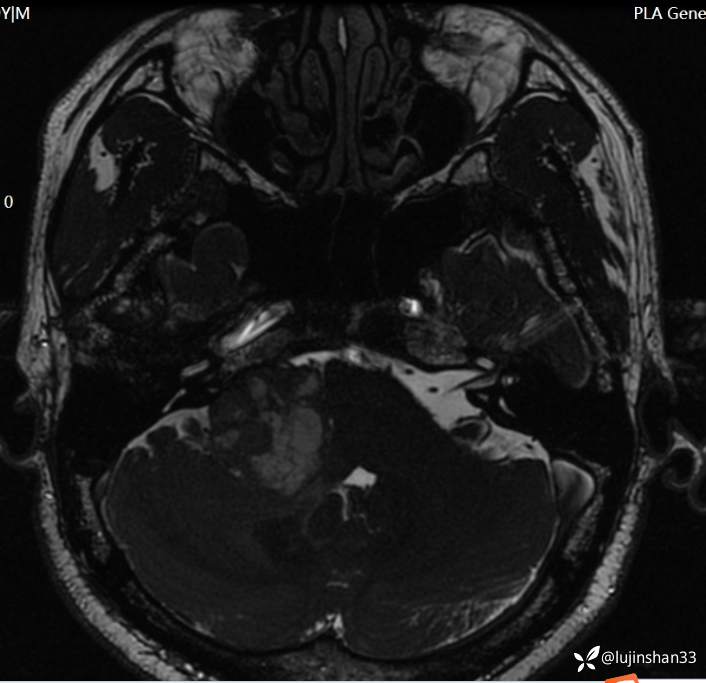

术后CT:

治疗经过:1.经迷路进路桥小脑角肿瘤次全切除+乙状窦后入路桥小脑角出血止血+腹部脂肪取出、术腔填塞术

2.因出血原因,瘤体有残留,术后7个月放疗